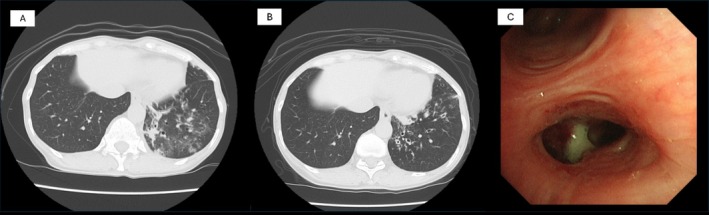

2019冠状病毒病(COVID-19)可导致呼吸系统后遗症,包括支气管扩张。虽然结核病后的支气管扩张是许多细菌感染/定植的滋生地,但很少有报道称COVID-19后的支气管扩张是细菌感染/定植的温床。我们报告了一例69岁的女性,她在COVID-19肺炎后出现支气管扩张。患者在新冠肺炎前5年胸部CT未见异常。她在COVID-19后出现持续咳嗽和痰,在COVID-19后的胸部CT显示新的支气管扩张。一年后,因慢性呼吸道感染反复加重,痰中检出流感嗜血杆菌,转至我科就诊。该病例突出了流感嗜血杆菌在covid -19后支气管扩张中感染/定植的可能性。虽然到目前为止,COVID-19后慢性气道感染合并支气管扩张的报道很少,但长期呼吸随访和细菌定植管理对这些患者未来至关重要。该病例提示,在支气管扩张的情况下,COVID-19可使个体易发生细菌感染,这强调了在COVID-19后气道管理中保持警惕的必要性。

Coronavirus Disease 2019 (COVID-19) can lead to respiratory sequelae, including bronchiectasis. While bronchiectasis following tuberculosis is a breeding ground for many bacterial infections/colonisation, there are few reports of bronchiectasis following COVID-19 being a hotbed for bacterial infection/colonisation. We present a case of a 69-year-old female who developed bronchiectasis following COVID-19 pneumonia. The patient had no abnormal findings on chest CT scan for 5 years before COVID-19. She developed persistent cough and sputum after COVID-19 and chest CT just after COVID-19 revealed new bronchiectasis. One year later, she was introduced to our department for repeating exacerbation of chronic respiratory infection, and Haemophilus influenzae was detected in sputum. This case highlights the potential for H. influenzae to infect/colonise in post-COVID-19 bronchiectasis. While there have been few reports of chronic airway infection complicating bronchiectasis after COVID-19 until now, long-term respiratory follow-up and management of bacterial colonisation are crucial in these patients in the future. This case suggests that COVID-19 can predispose individuals to bacterial infection in the setting of bronchiectasis, emphasising the need for vigilance in post-COVID-19 airway management.